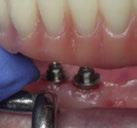

Ejecución técnica quirúrgica mediante férula guiada Bajo anestesia infiltrativa realizamos extracciones atraumáticas de todas las piezas a excepción de los dientes que actúan como anclaje o pilares para la fijación de la férula quirúrgica (Figuras 20 y 21). Seguidamente insertamos la férula comprobando una buena adaptabilidad y estabilidad

(Figuras 22 y 23). Se realiza fresado transgingival mínimamente invasivo y guiado hasta la inserción de los implantes, siguiendo el protocolo preestablecido e indicado (Figuras 24 a 26).

Durante la colocación de los implantes comprobamos una inserción con torque superior a 35 N/cm2

Retiramos la férula y comprobamos una correcta estabilidad primaria mediante mediación de valores

ISQ favorables en la mayoría de los implantes. Seguidamente se extraen los dientes remanentes que han actuado de medio retentivo para la férula quirúrgica.

Dentro de la fase quirúrgica propiamente dicha, una vez terminada la inserción de los implantes y

comprobada su estabilidad primaria, colocamos pilares transepiteliales

Multiplus para registrar una impresión digital mediante escaneado sobre ellos (Figuras 27 a 29)